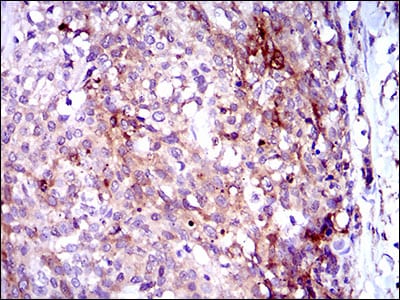

分类: 科研抗体货号: 30521别名: MRP4; MOATB; MOAT-B; EST170205应用: IHC,FCM反应种属: Human

分类: 科研抗体货号: 30526别名: MRP4; MOATB; MOAT-B; EST170205应用: IHC,FCM反应种属: Human